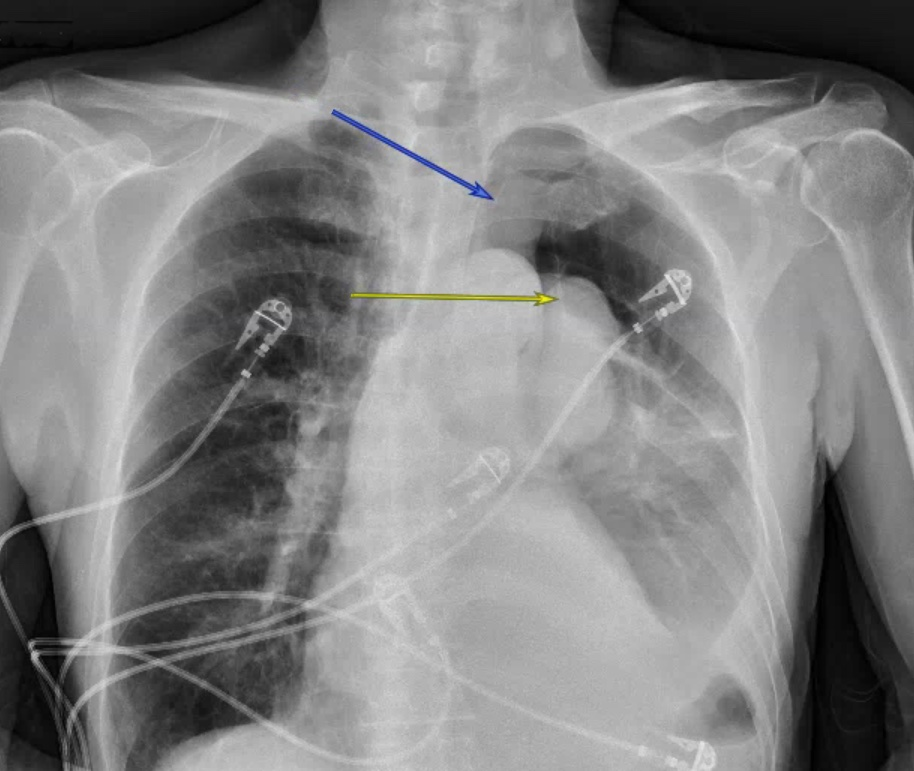

A 71 year old male presents with a chief complaint of dyspnea on exertion. He appears to be in no distress. His vital signs are stable. A CXR is ordered. What's the diagnosis? (scroll down for answer)

Answer: Pneumothorax secondary to bleb rutpure

- This CXR demonstrates a spontaneous pneumothroax contained to the left upper lobe secondary to bleb rupture

- Diagnosis confirmed by CXR or CT chest (when uncertain of diagnosis on CXR or to determine size of PTX)